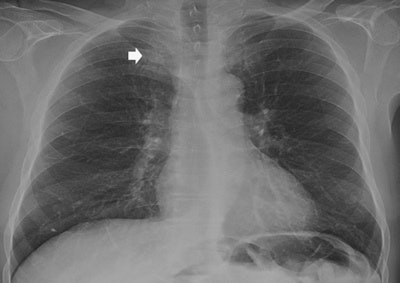

Detecting and characterizing pulmonary lesions, particularly pulmonary nodules, on chest radiography (CXR) is challenging, because of their frequently small size and poor conspicuity within surrounding anatomical structures. Pulmonary lesions are often visible only retrospectively when reviewing previous radiographic images of patients with known nodules, and computer-aided detection (CAD) systems have been advocated to improve the diagnostic accuracy, according to Dr. Emilio Quaia, from the radiology department at Cattinara Hospital, University of Trieste in Italy, and colleagues.

"Frequently, the radiologist reporting CXR identifies doubtful or equivocal findings that could be referred to as both pulmonary and extrapulmonary lesions, or also as pulmonary pseudolesions because of different planes overlapping or composite areas of increased opacity," they wrote in a study published in Insights into Imaging (14 January 2014).

Compared with CXR, digital tomosynthesis produces superior images for identifying the intra- or extrapulmonary lesions previously suspected based on initial CXR interpretation. It also removes overlying anatomical structures, enhances local tissue separation, and provides more depth of information of the structure of interest. And it has a lower radiation dose than CT.

In 229 of 465 patients who underwent digital tomosynthesis after suspicious CXR, digital tomosynthesis showed 193 pulmonary lesions and 36 pleural lesions. In the remaining patients, lesions were ruled out as pseudolesions on CXR.